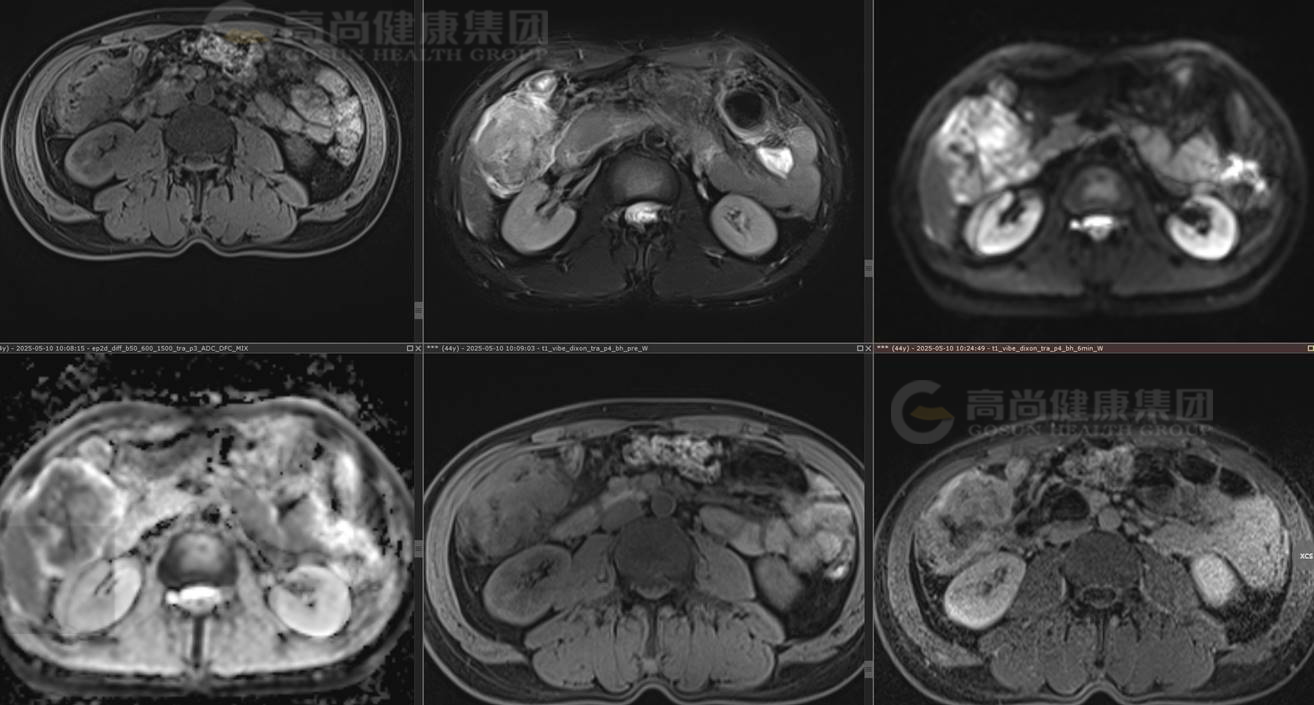

MRI图像

结肠肝曲肠壁增厚,肠腔狭窄,T1WI低信号、T2-FS高信号,DWI高信号、ADC低信号(弥散受限),增强扫描不均匀中度强化。

MRI诊断意见:

结肠肝曲占位,考虑肿瘤性病变,结肠癌可能性大,伴邻近肠系膜受侵,肠管周围小淋巴结可疑转移,建议结肠镜及PET/CT检查。